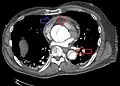

Computed tomography angiography is a fast, non-invasive test that gives an accurate three-dimensional view of the aorta. These images are produced by taking rapid, thin-cut slices of the chest and abdomen, and combining them in the computer to create cross-sectional slices. To delineate the aorta to the accuracy necessary to make the proper diagnosis, an iodinated contrast material is injected into a peripheral vein. Contrast is injected and the scan performed using a bolus tracking method. This type of scan is timed to injection to capture the contrast as it enters the aorta. The scan then follows the contrast as it flows through the vessel. It has a sensitivity of 96 to 100% and a specificity of 96 to 100%. Disadvantages include the need for iodinated contrast material and the inability to diagnose the site of the intimal tear.

-

CT with contrast demonstrating aneurysmal dilation and a dissection of the ascending aorta (type A Stanford) - Chest CT with descending (type B Stanford) aortic dissection (red circle)

Type A dissection with pericardial effusion as a result.